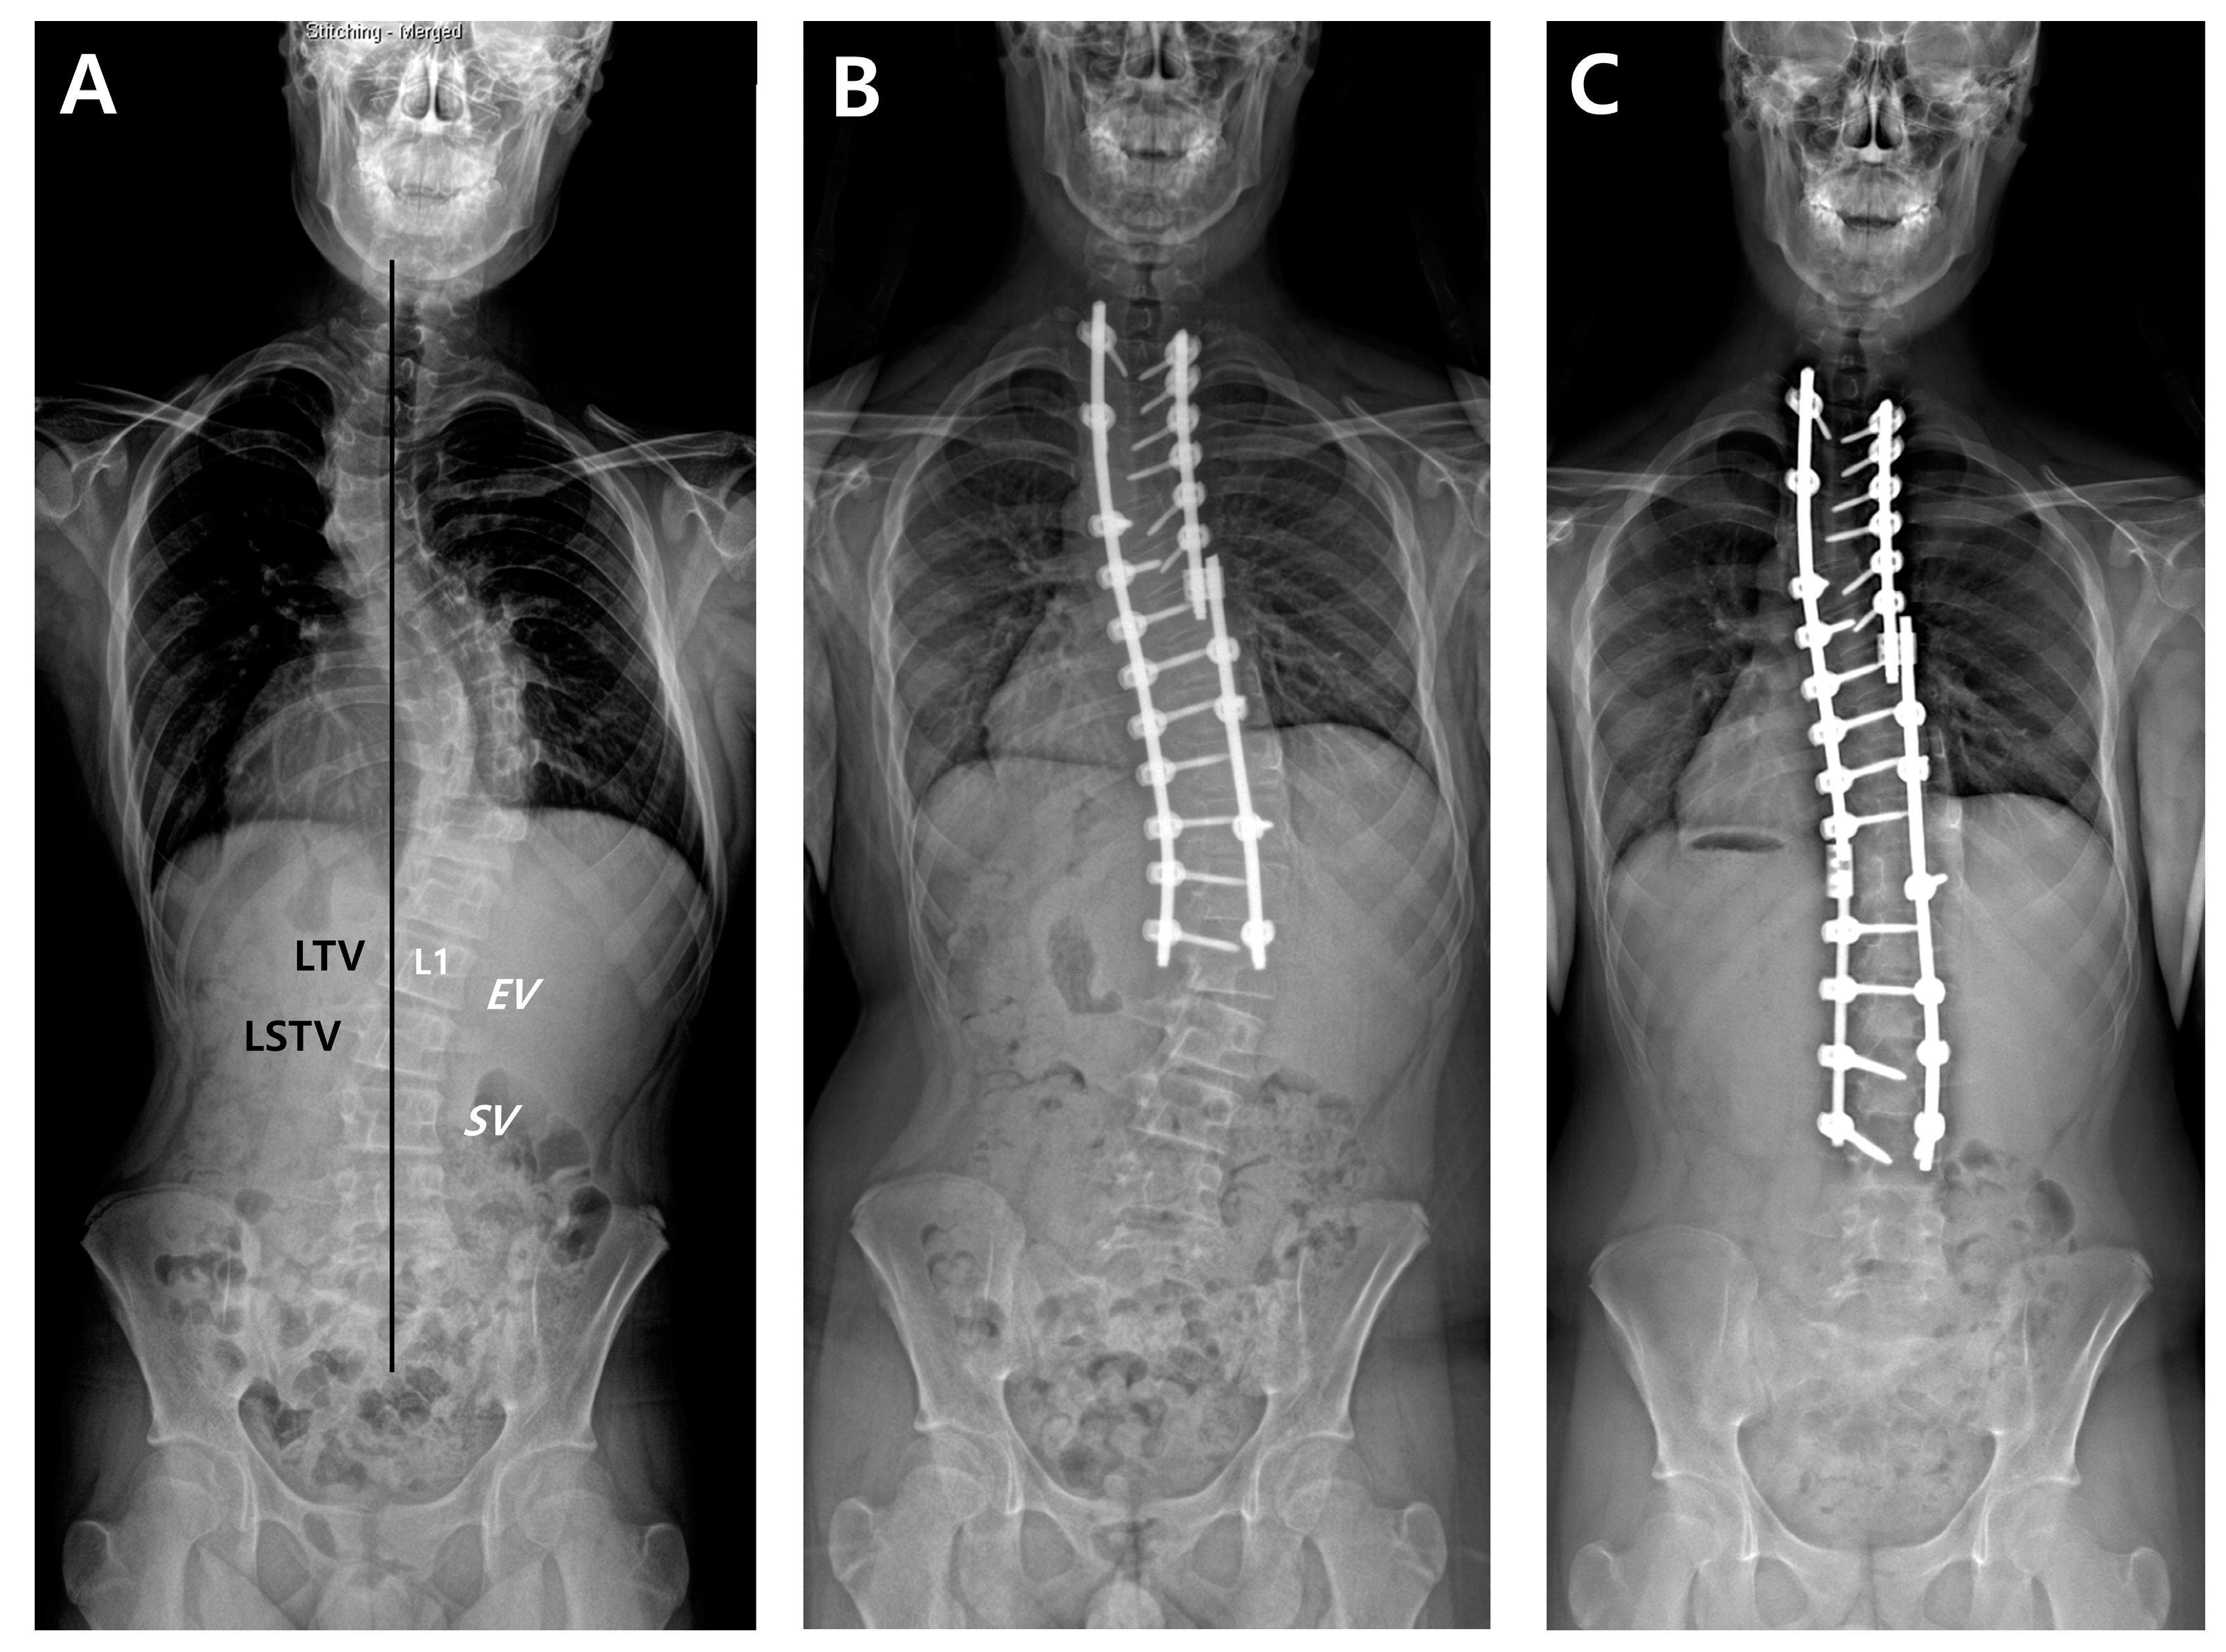

2.4. Radiographic Measurements

For all patients, whole-spine standing posteroanterior, lateral, and fulcrum bending radiographs were taken preoperatively. After surgery, standing posteroanterior and lateral whole-spine radiographs were performed at six weeks, three months, six months, and then annually as part of a routine evaluation of all scoliosis cases. First, we designated radiographic parameters such as EV, NV, and SV on a preoperative whole-spine AP radiograph (Figure 1). The last touching vertebra (LTV) and last substantially touching vertebra (LSTV) were measured using CSVL. On the same radiograph, the nine suggested LIVs according to the selection criteria were separately recorded. Then, we compared the location of suggested LIVs and the actual LIV, and evaluated whether the actual LIV was the same, proximal, or distal relative to the suggested LIV. DA was defined as a progressive increase in the number of vertebrae included within the distal curve, with either an increase of more than 5 mm in the deviation of the first vertebra below the instrumentation from the CSVL or an increase of more than 5° in the angulation of the first disc below the instrumentation [7]. Finally, the preoperative Cobb’s angle (CA) of the main thoracic curve (MTC), flexibility of the MTC, postoperative CA of the MTC, and correction rate of the MTC were measured.

Figure 1.

A thirteen-year-old male underwent posterior fusion from T1 to L1 for AIS of Lenke type 2A curves (A,B). Revision surgery with fusion extension to L3 was carried out due to the development and progression of DA (C). According to the nine LIV selection criteria, the postoperative actual LIV (L1) met the criteria by Wang, Sarlak, Matsumoto, and Fischer. The location of the postoperative LIV was proximal to the suggested LIVs by King (L3), Suk (L3), Parisini (L2), Takahashi (L4), and Qin (L2).